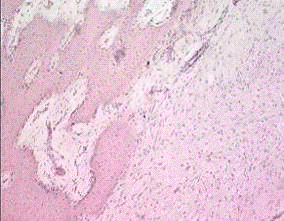

Особенности репаративной регенерации костной ткани после огнестрельных

переломов заключаются в массивности повреждения с гибелью большого числа

костных клеток, выраженности воспалительных и дегенеративных процессов с

развитием явлений остеопороза, особенно выраженные в дистальном отломке. Авторы

отмечают, что часть оставленных в ране костных осколков, преимущественно самые

мелкие, претерпевают явления некроза, деструкции и лизиса. Большинство же крупных

осколков сохраняет свою жизнеспособность и в них отмечаются признаки

новообразования костной ткани. Также обращает на себя внимание преобладание в

гистоструктуре регенерата соединительно-тканной компоненты, а также замедление

формирования костной ткани по сравнению с регенерацией обычного перелома - лишь

к 45-м суткам начинают обнаруживаться очаги формирования первичных остеонов,

лишенных упорядоченного строения и ориентации. К 90-м суткам отмечается наличие

небольшого по объёму периостального регенерата, преобладание между осколками

гиалиновой и волокнистой хрящевой, а также плотной волокнистой соединительной

ткани.

В регенерате даже на 120-е сутки преобладает плотная волокнистая

соединительная ткань с наличием зон имеющих высокую степень упорядоченности

расположения коллагеновых волокон, а также с наличием участков волокнистого

хряща. В ретикулофиброзной ткани отмечается наличие неактивных остеобластов и

остеоцитов, а также, напротив, активных остеокластов, что свидетельствует о

продолжающихся процессах резорбции и ремоделирования.